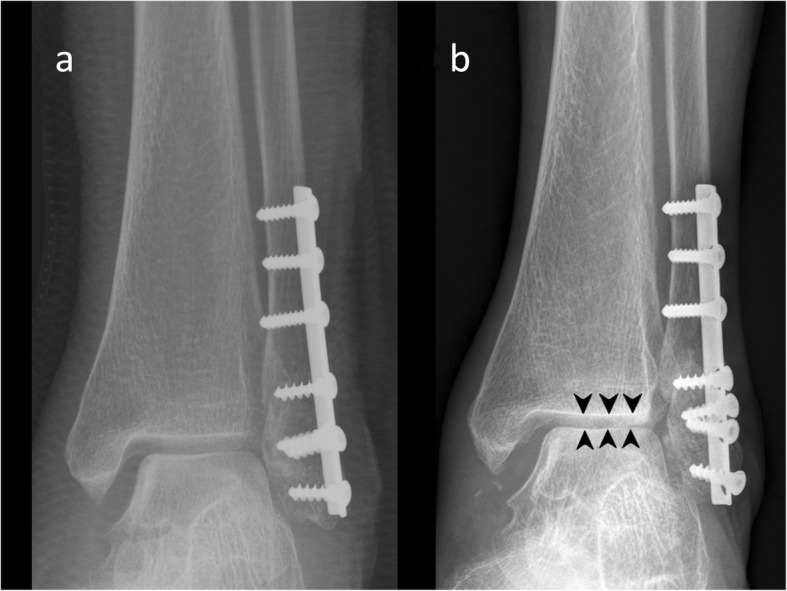

At the end of the 1-year follow-up, the VAS score, FAOSs, and radiological outcomes (Figs. 2 and 3) of each patient were compared and analyzed with those recorded immediately postoperatively.

Fig. 3.

This 78-year-old woman was treated with an interfragmentary screw and a TP. During securing of the interfragmentary screw, the far cortex was cracked, and absolute stability was not achieved. The fibula length could not be anatomically maintained using a TP that was not a fixed angle device. a Finally, the reduction accuracy was fair (immediately postoperative radiograph). b One year later, it was malunited (the medial ankle-joint substantially widened), the OA grade worsened (arrowheads), and all distal screws were loosened